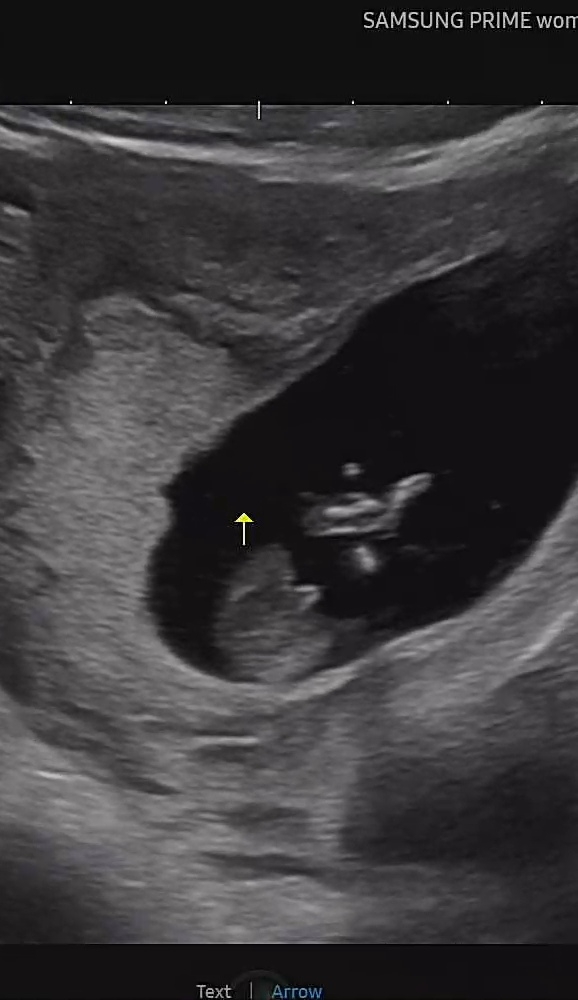

가운데 보이는게...맞죠?

너무🌶같아서요..ㅎㅎ

아근데 이건 좀 애매한거같아요! 아들은 점세개보인댔는데 두줄이라..ㅎㅎ